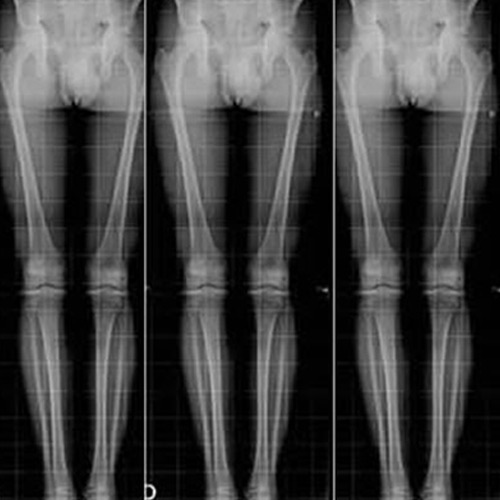

Escanograma

digital directo

Estudio de los miembros inferiores completo comparativo para la evaluación de la morfología y asimetrías para su adecuada planificación terapéutica.